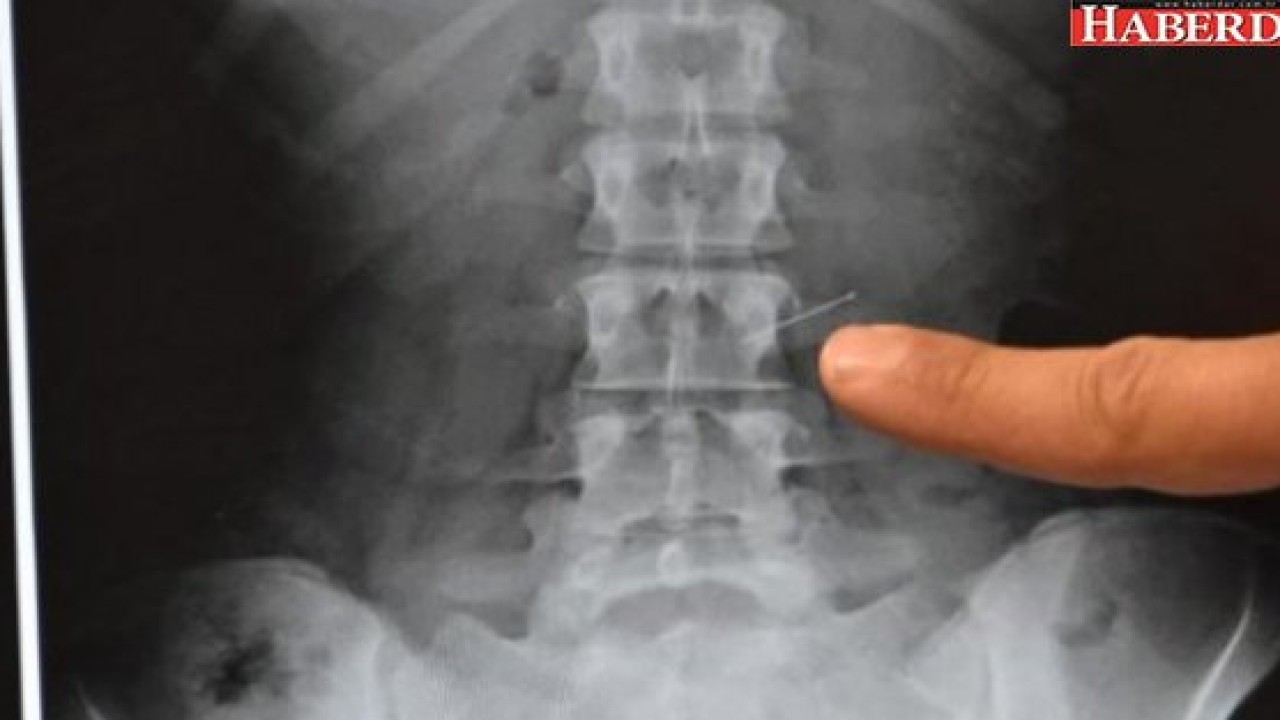

Konya'nın Ilgın İlçesi'nde 18 yaşındaki İlayda Adıgözel, kursa gitmek için hazırlanırken, eşarbını tutturmak için ağzında tuttuğu 3 toplu iğneden birini öksürünce yuttu. Hastaneye götürülen genç kızın midesindeki iğne yapılan operasyonla alındı.

Özel Farabi Hastanesi'ne getirilen genç kız hemen ameliyata alındı. Endoskopi yöntemiyle İlayda Adıgözel'in midesinde bulunan toplu iğne çıkartıldı. İlayda Adıgözel yaşadıklarını şöyle anlattı:

Operasyonu gerçekleştiren Genel Cerrahi Uzmanı Dr. Bülent Erenoğlu, "Bize vakit kaybetmeden geldi. Biz de endoskopiyle müdahale ettik ve iğneyi başarılı bir şekilde çıkardık. İğne birkaç yerde zedeleme yapmış, onun dışında bir problem yok" dedi.